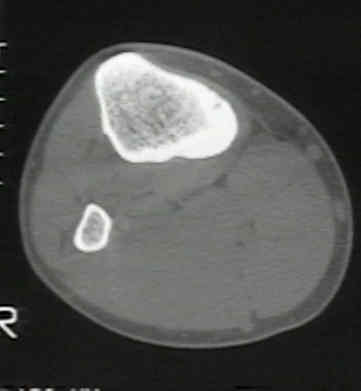

TAC:

El nidus se localiza mejor con  la CT, dicen los radiólogos, para el diagnóstico diferencial.

Los cortes deben ser de 1-2 mm para visualizar el nidus

Deben ajustarse las escenas de la ventana del escáner de CT para que la reacción densa alrededor de la lesión no disimule el pequeño nidus de densidad baja.

Ver imagen